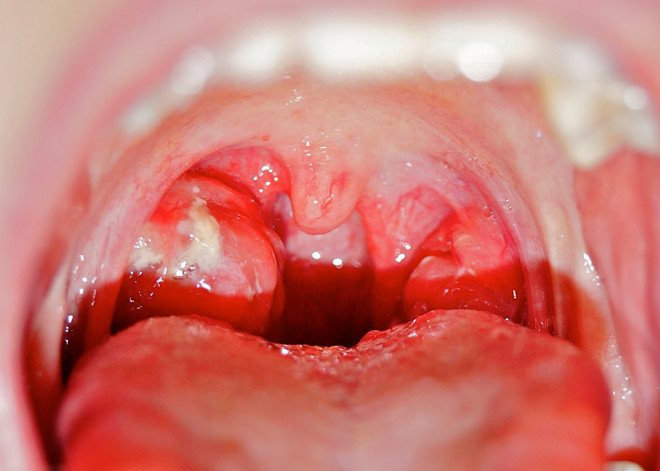

Viêm họng có thể gây ra một số biến chứng như viêm cầu thận cấp, thấp tim, viêm khớp cấp. (Ảnh: Seoarticlelibrary)